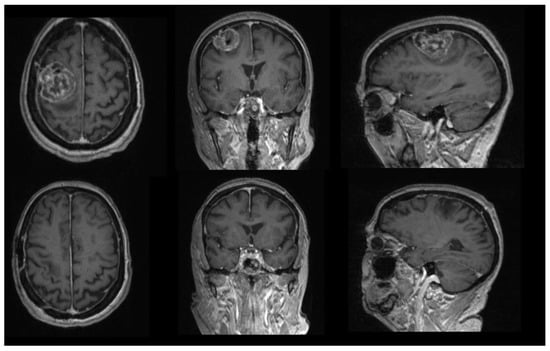

- Mandel, M.; Li, Y.; Figueiredo, E.G.; Teixeira, M.J.; Steinberg, G.K. Presurgical Planning with Open-Source Horos Software for Superficial Brain Arteriovenous Malformations. World Neurosurg. 2021, 157, 3–12. [Google Scholar] [CrossRef]